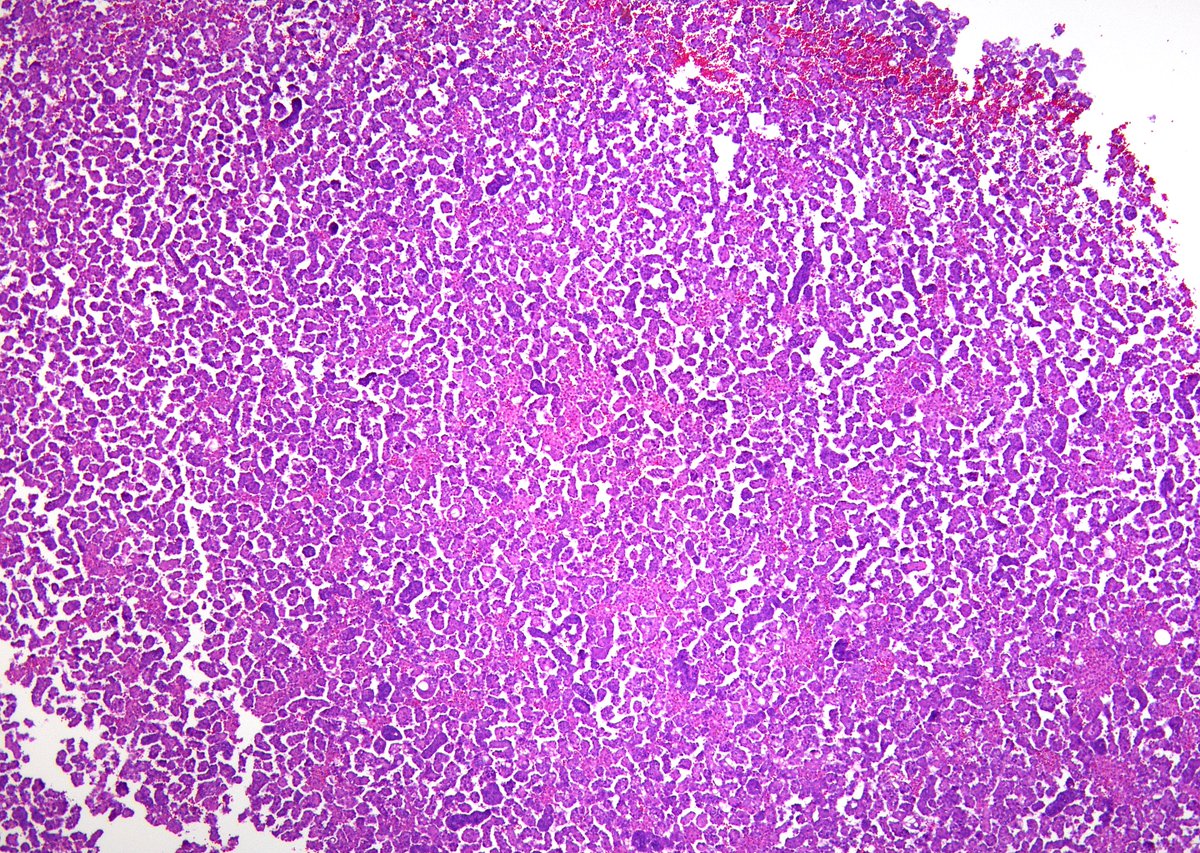

I'm always amazed 😮at how Small CC appears on smears (EBUS-FNA, lung)🫁 🔬Fine/dark chromatin 🔬Absent/inconspicuous nucleoli 🔬Scant/absent cytoplasm 🔬Apoptotic bodies 🔬Paranuclear blue bodies (arrow): dense collections of keratin filaments @IACytology @CytologyEFCS

3

54

124